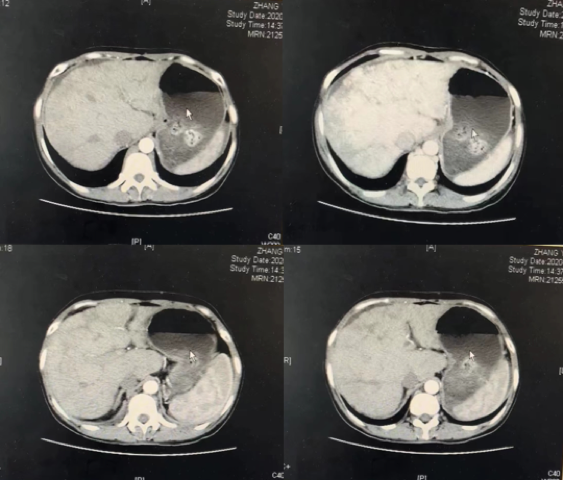

2021年8月复查CT示(图6),肝右叶示直径约3.6cm结节状稍低密度影,中央及周围示斑片、斑点状高密度影,动脉期周围斑片状病灶强化,静脉期及延迟期密度减低。复发转移?

图6.2021年8月复查CT